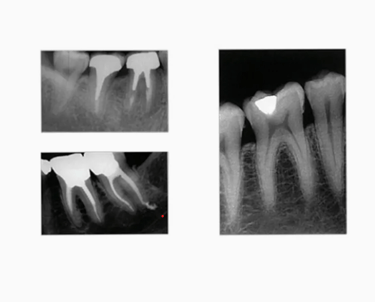

Portable dental X-ray machines are compact, mobile devices used for imaging teeth and surrounding bone structures in dental clinics, hospitals, or even in patients' homes. They are designed to be easy to use and provide high-quality radiographic images, but with controlled radiation exposure. These devices help dental professionals in diagnosing various oral conditions such as cavities, infections, bone loss, and abnormalities.

Many portable X-ray machines now come equipped with digital sensors, allowing for high-resolution images. These images can be stored and shared electronically, reducing the need for physical film and improving diagnostic efficiency.

Digital technology in portable dental X-ray machines provides superior image quality, which aids in accurate diagnosis and treatment planning.